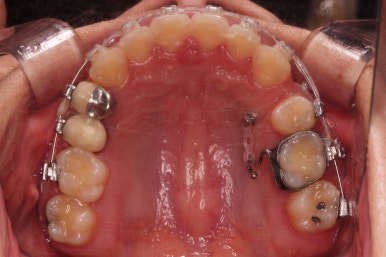

초진 시 입안의 모습을 보실게요.

결국은 앞니 사이에 틈이 생겼기 때문에 이같은 문제점을 인지하시고 내원하셨던거죠.

우선 장치를 부착했습니다.

이번에 선택한 장치는 엠파워 클리어라고 하는 자가결찰 세라믹 장치인데요.

흔히 아시는 클리피씨 장치와 같은 분류의 장치입니다. 클리피는 일본, 엠파워는 미국 제조사라는 차이가 있지만 큰 틀에서는 세라믹 바디에 금속 클립이 달린 거의 동일한 장치라고 보시면 됩니다.

장치 부착 직후의 모습인데요.

장치가 보이는 느낌이나 옆라인의 변화 양상은 참고해 주세요.